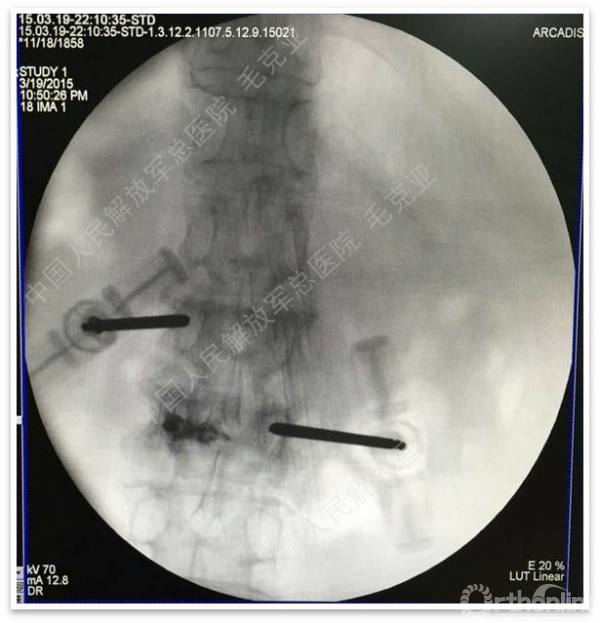

导语:随着社会老龄化的不断加速,骨质疏松性椎体压缩骨折作为一种普遍存在的老年骨科疾病已经成为现今骨科界的一个热点话题。传统的保守疗法治疗效果不佳,而现有的椎体增强技术又具有多种风险和缺陷。针对这种现状,中国人民解放军总医院毛克亚教授提供了一种新的解决方法。